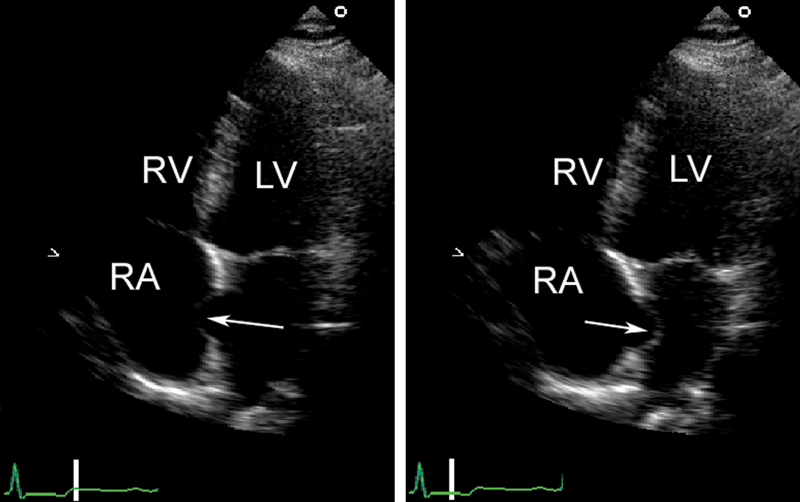

فحوصات تشخيصية لبعض امراض القلب والشرايين التاجية